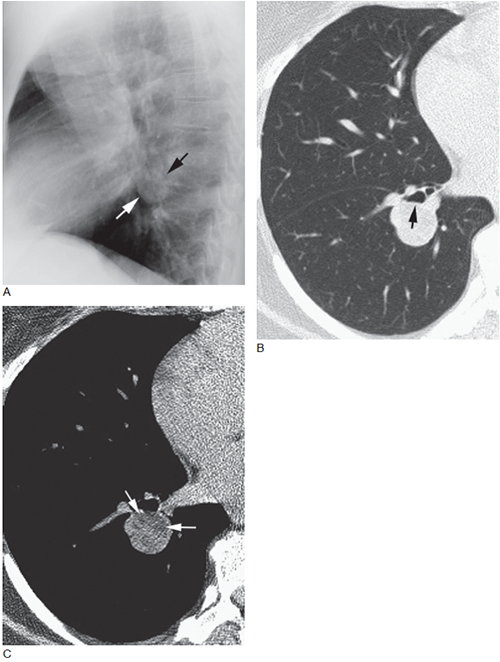

图1 支气管内的错构瘤

A. 侧位片显示,边界清楚的肺门结节( 箭头);B. 肺窗上的高分辨率CT 显示边缘锐利的肺门结节压迫右下叶支气管使其狭窄;C. 软组织窗的高分辨率CT 显示含有脂肪区域(-80Hu)( 箭头),在错构瘤中常见